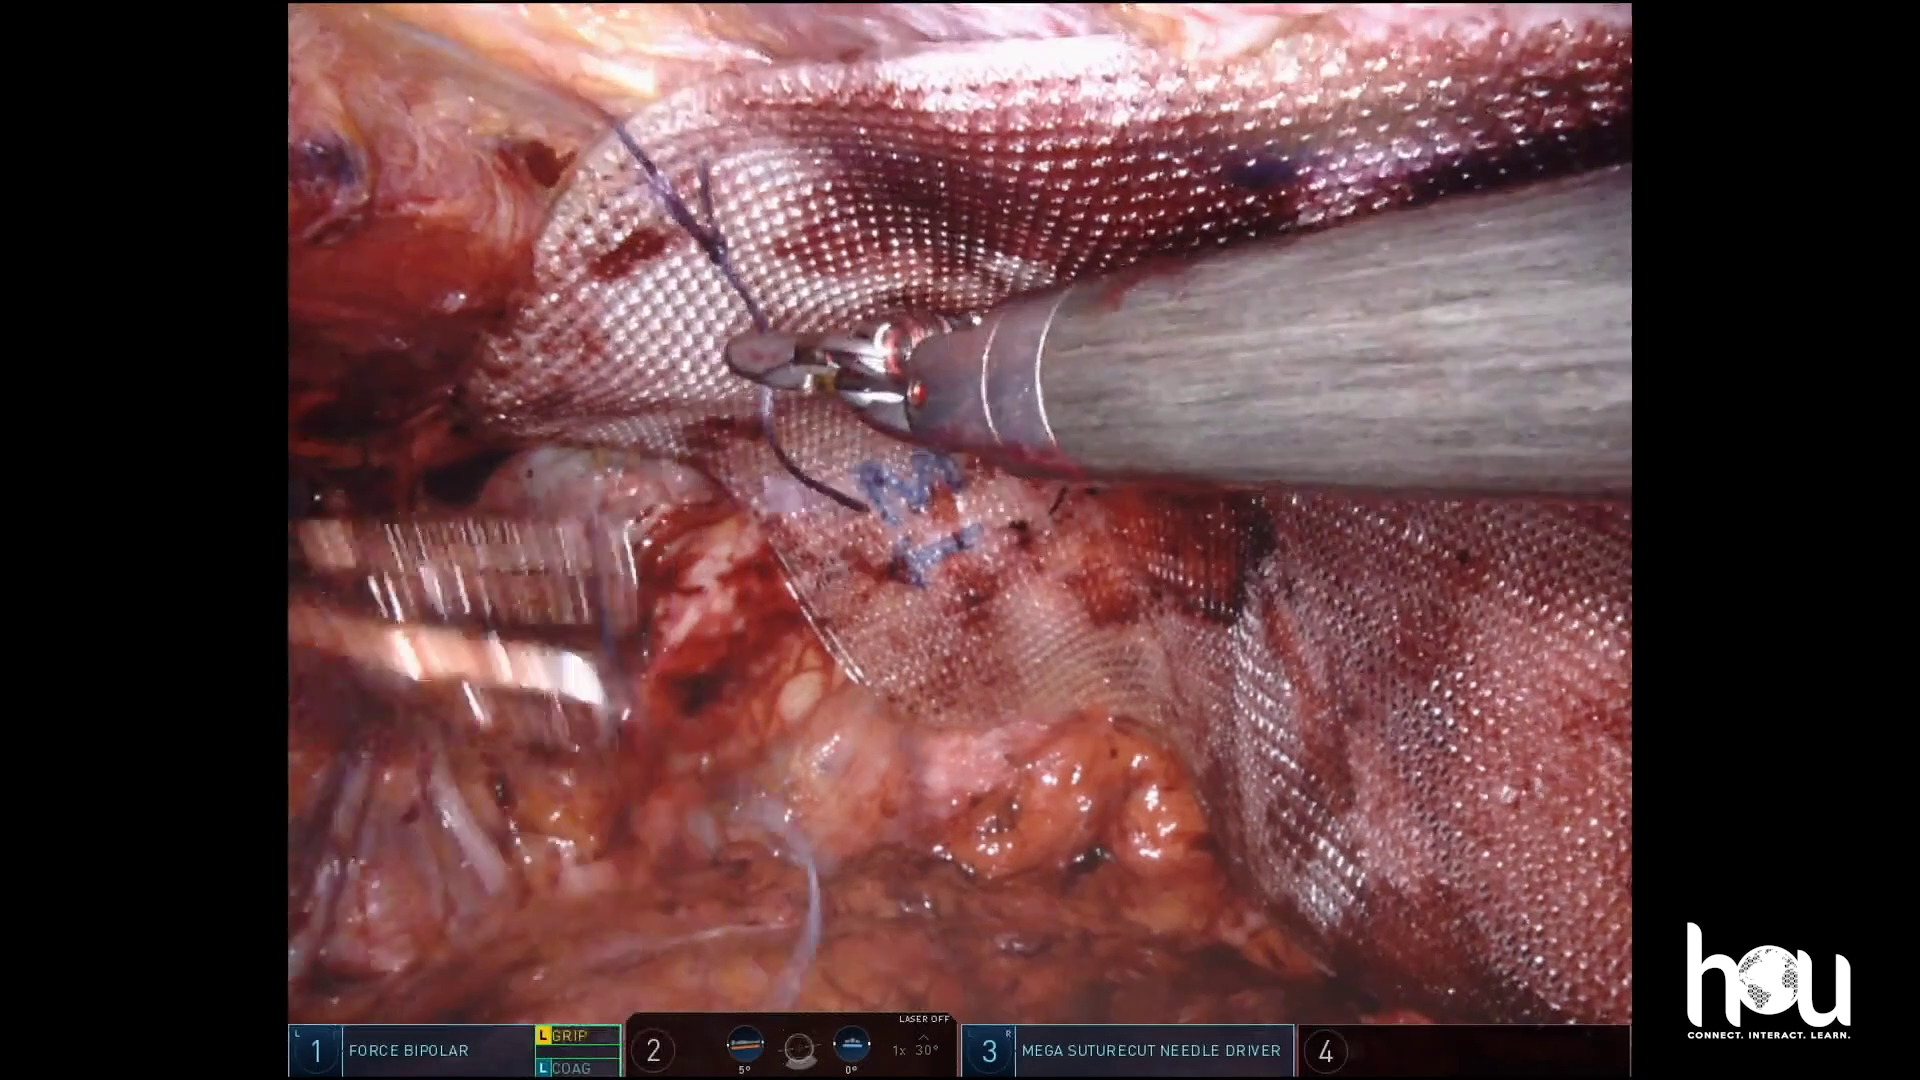

Dr. Malcher | Robotic ventral hernia repair with rectus diastasus

Doctor(s): Dr. Malcher Description of of the case: Minimally edited video on robotic extraperitoneal access for a ventral hernia repair with rectus diastasus [...]